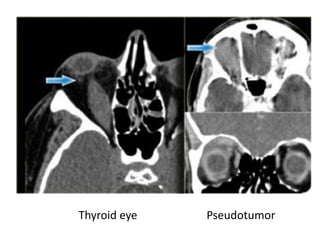

Conal space pathology

• Thyroid eye disease

– usually enlargement of the inferior and medial rectus

• Pseudotumor:

– idiopathic orbital inflammation

Thyroid opthalmopathy

• Compressive optic neuropathy

– Direct compression by the muscles

– Ischemic by compression of the vessels

Idiopathic inflammatory pseudotumor

• Idiopathic inflammation of the orbit

• Any part of the orbit: muscles, tendons, fat, optic

nerve, nerve sheet, lacrimal gland

Pseudotumor

Thyroid eye Pseudotumor